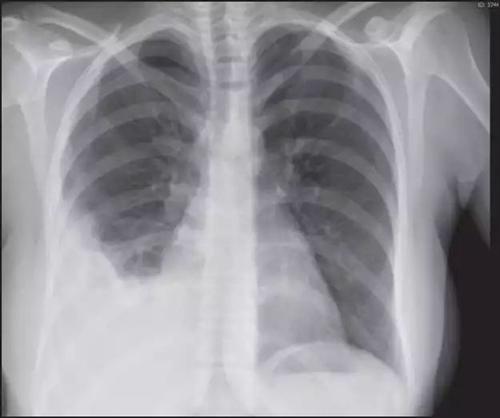

那么,胸膜炎是如何引起的呢?一般来说,有三种原因。生活中,不少人感冒后会出现胸痛、呼吸困难等症状,这可能是患上了胸膜炎。3.胸膜炎:胸膜炎指发生在胸膜腔的炎症,主要与感染、自身免疫、恶性肿瘤等因素有关,可出现胸痛、胸膜等典型症状,且常在深咳嗽时出现,从而出现咳嗽心疼的表现。

咳嗽腋下痛是怎么回事咳嗽腋下痛可能是某些疾病的表现症状,如肺炎、胸膜炎、肋间神经痛等,应及时就诊查明病因。胸膜炎的常见症状有哪些呢?谢医师健康科普:常见症状:胸闷气短、咳嗽、畏寒发热。

2.胸膜炎:发生在胸膜腔内的炎症,常以发热、咳嗽、咳痰、胸痛、胸闷及呼吸困难为主要临床表现,也可能出现腋下痛。咳嗽心疼是怎么回事咳嗽心疼可由生理因素、心绞痛、胸膜炎等因素引起。

能够引起胸痛的原因有很多,如胸膜炎、肺脓肿、肋软骨炎症、心包炎、心绞痛、心梗等。除肺炎外,一些其他疾病也可以引起咳嗽伴咳白痰症状,例如慢性支气管炎、间质性肺病、支气管哮喘、胸膜炎、肺癌等,因此仅凭症状无法明确诊断,需要完善胸片、ct、血常规、痰培养等相关检查化验进一步明确诊断。